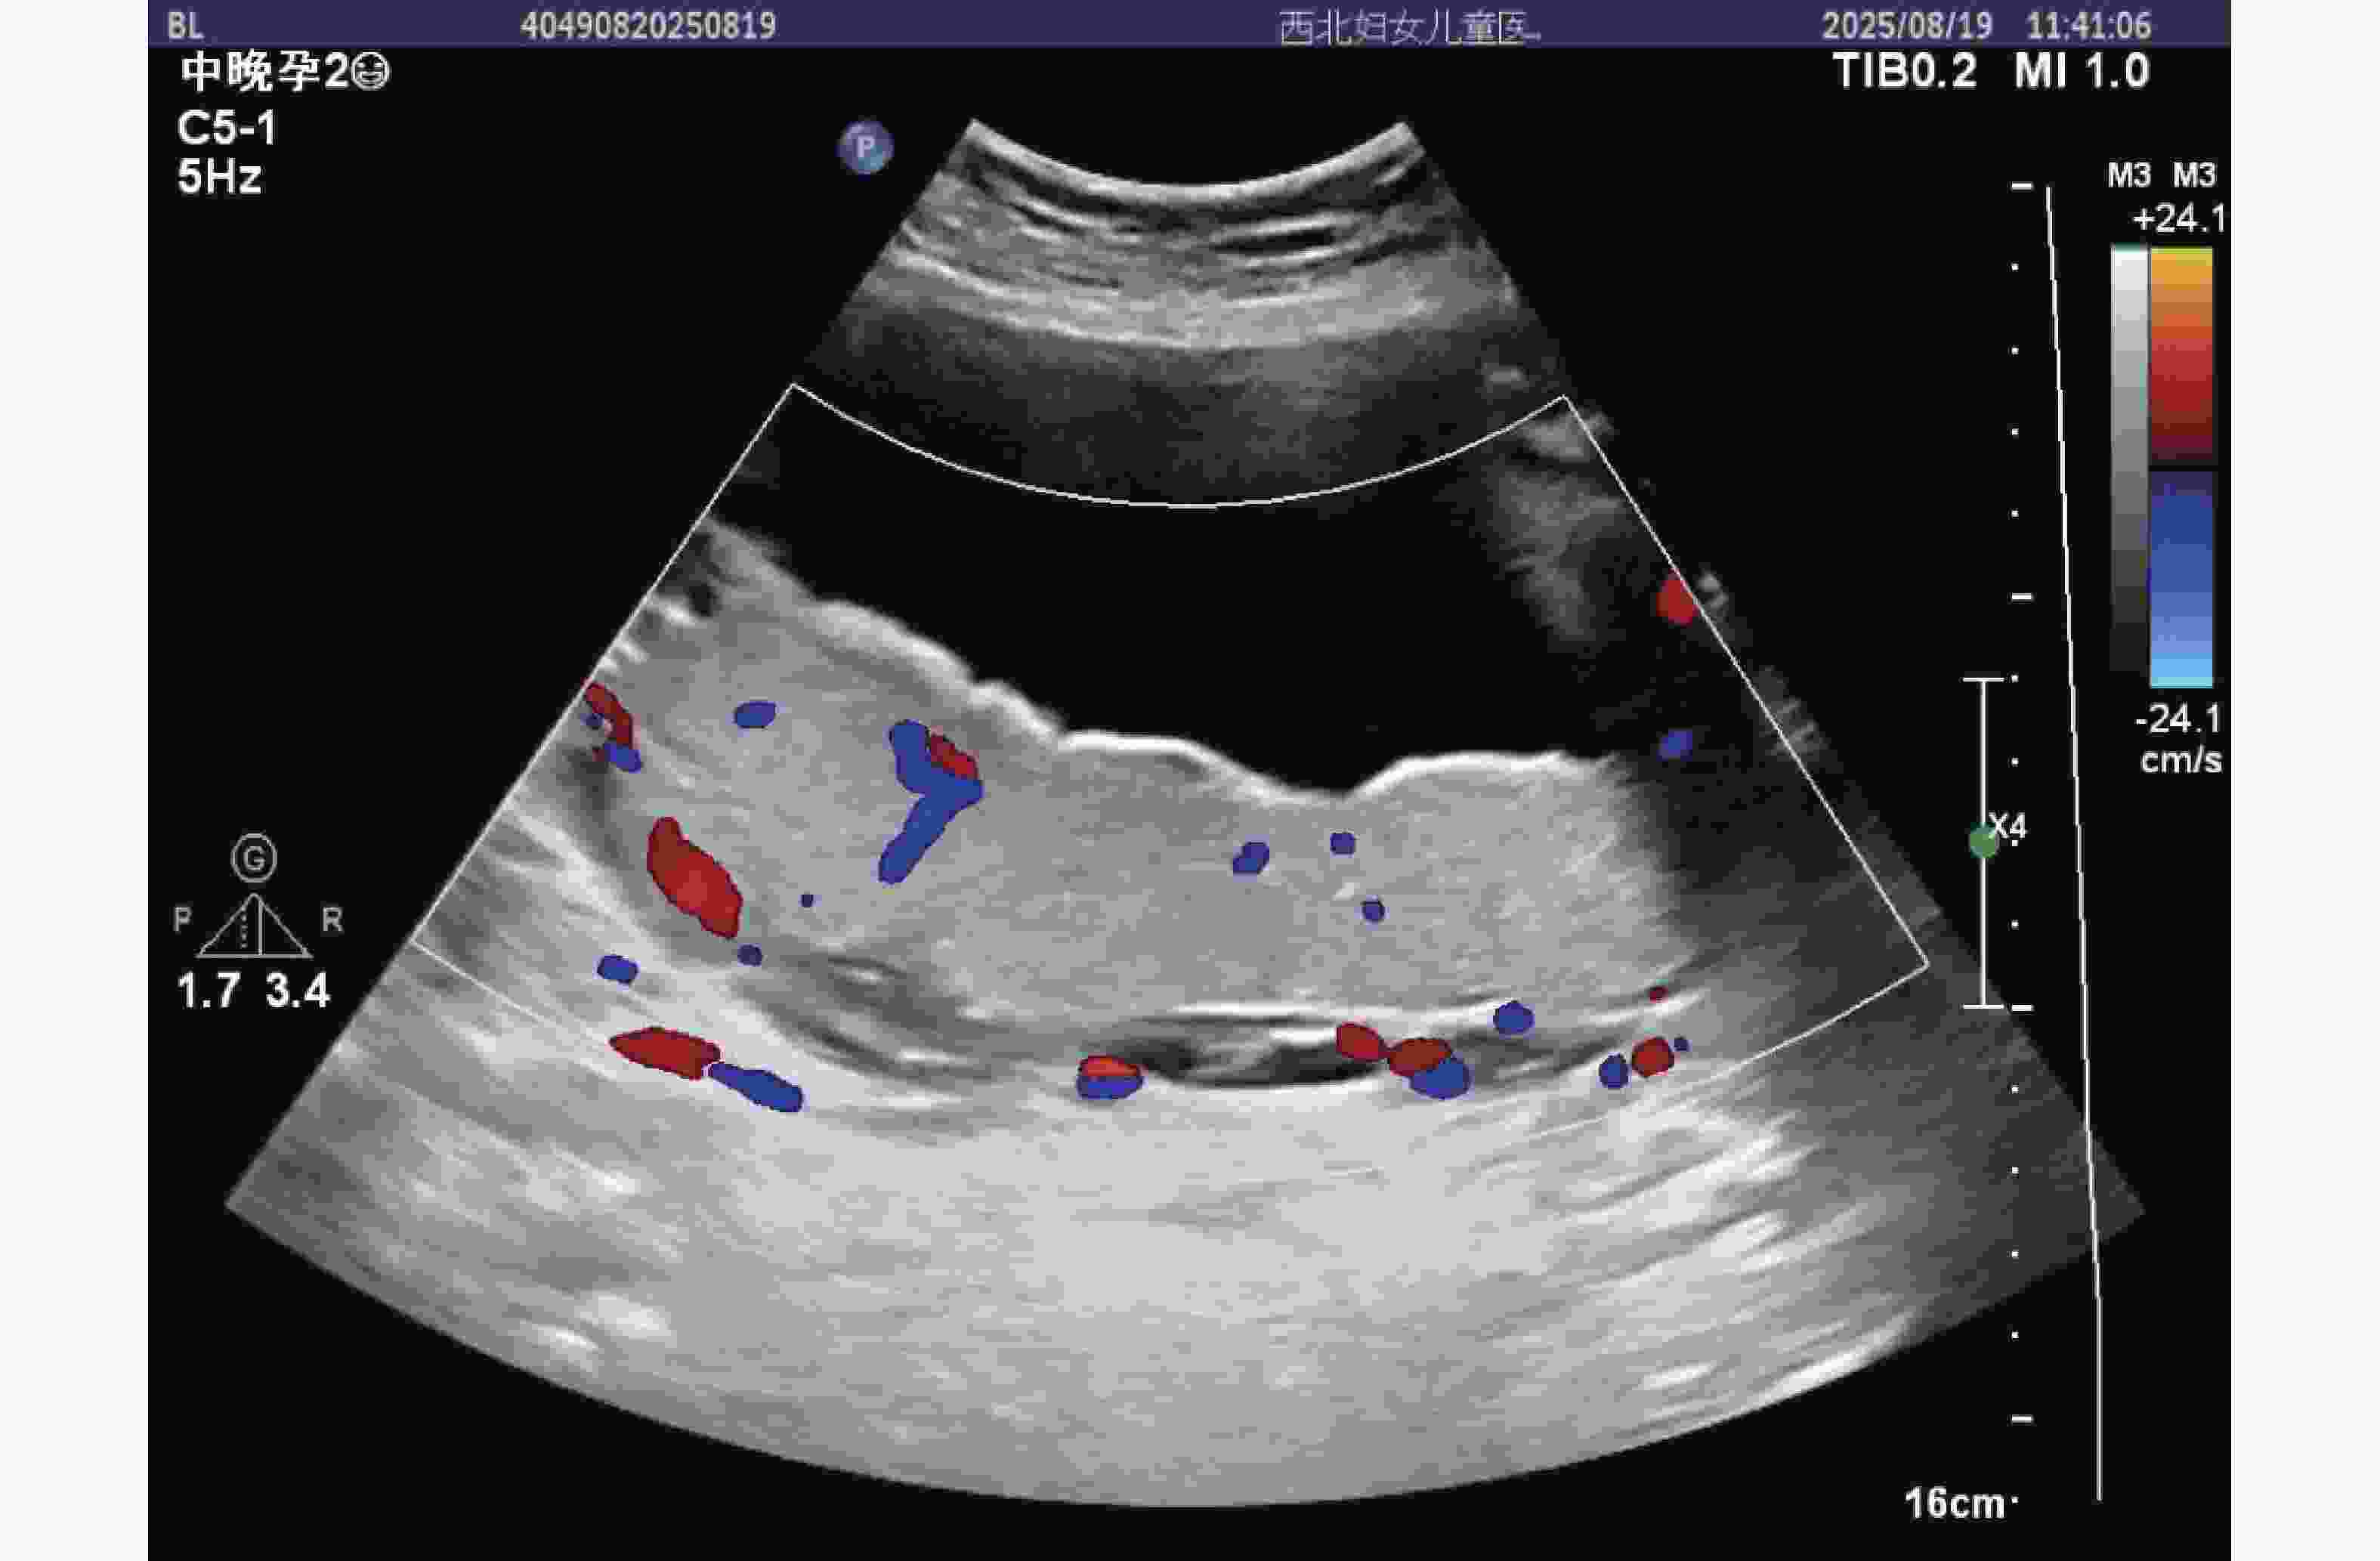

图  3  孕中期子痫前期孕妇胎盘超声影像

注:胎盘表面可见散在点状强回声(红色箭头指示),提示早期钙化倾向;彩色多普勒显示胎盘小叶间血流分支减少,血流信号强度减弱,反映胎盘血管床发育不良,灌注能力下降。

Figure  3.  Ultrasound image of the placenta in a pregnant woman with preeclampsia in the second trimester of pregnancy